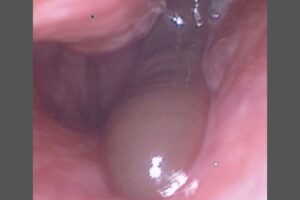

Other A Refreshing Mountain Rinse Left This Man With a Nose Leech and Days of Bleeding By gizmodo.com - October 30, 2025 Share on Facebook Tweet on Twitter A Refreshing Mountain Rinse Left This Man With a Nose Leech and Days of Bleeding “Nasal leeches” are an uncommon source of nosebleeds, his doctors wrote in a recent case report. read more Source: www.gizmodo.com RELATED ARTICLES Google DeepMind Gets Into Gaming, Purchases Stake in the Company Behind EVE Online This Experimental Low-Waste Fuel Could Transform Nuclear Reactors ‘Fantastic Four’ Director Matt Shakman Will Helm Next ‘Planet of the Apes’ Movie ‘The Testaments’ Just Brought Back Another Surprising ‘Handmaid’s Tale’ Character Ford Is Trying to Beat China and Bring a $30,000 Truck to the U.S. The Russos Say Making Spider-Man Responsible for Uncle Ben’s Death Would’ve Made Him Too ‘Intense’ Watch NASA’s Curiosity Rover Struggle to Break Loose From a Rock on Mars Google Chrome Is Downloading a 4GB AI Model Onto Your Device Without Consent, Researcher Warns ‘Widow’s Bay’ Reveals the Perils of Dating on a Cursed Island